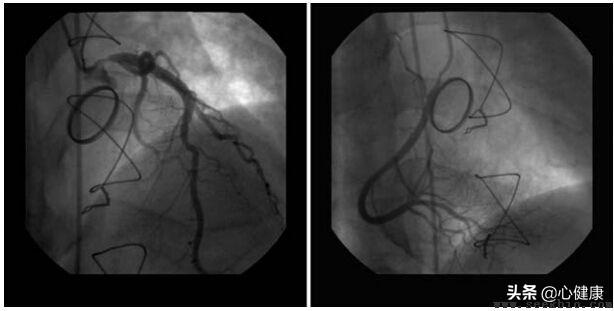

急性心筋梗塞は冠動脈疾患の中で最も攻撃的なタイプである。冠動脈内のアテローム性プラークが破裂し、血管を塞ぐ血栓が形成されるのが主なタイプで、血管を再開通させるためにしばしば緊急事態が必要となる。血管を再開通させる最善の方法はPCIである。

PCIは経皮的冠動脈インターベンションとして知られ、画像診断、バルーン拡張、ステント留置を含む一連の行為を含む。急性心筋梗塞患者に対しては、すべてではないが、ほとんどの場合、PCI後にステントが留置される。

血栓が血管をふさいでいても、プラーク自体はそれほど深刻でない患者もおり、その場合は血栓を取り除くだけで十分で、ステント留置の必要はない。